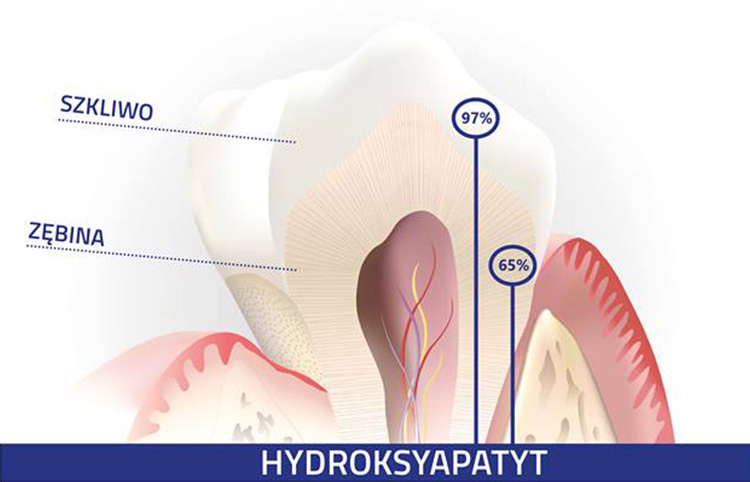

Aż 68% zębiny i 97% szkliwa zębów stanowi minerał o nazwie Hydroksyapatyt. Zawarty w produktach Prevdent nano-Hydroksyapatyt jest mniejszą wersją tego minerału i posiada zdolność łączenia się z Hydroksyapatytem obecnym w zębach. Przenikając głęboko do kanalików zębiny nHAp eliminuje nadwrażliwość, przy jednoczesnej remineralizacji i odbudowie uszkodzonego szkliwa. Powierzchnia zębów staje się znów gładka i błyszcząca. Szkliwo zostaje odbudowane a bolesna nadwrażliwość w dużej mierze wyeliminowana.